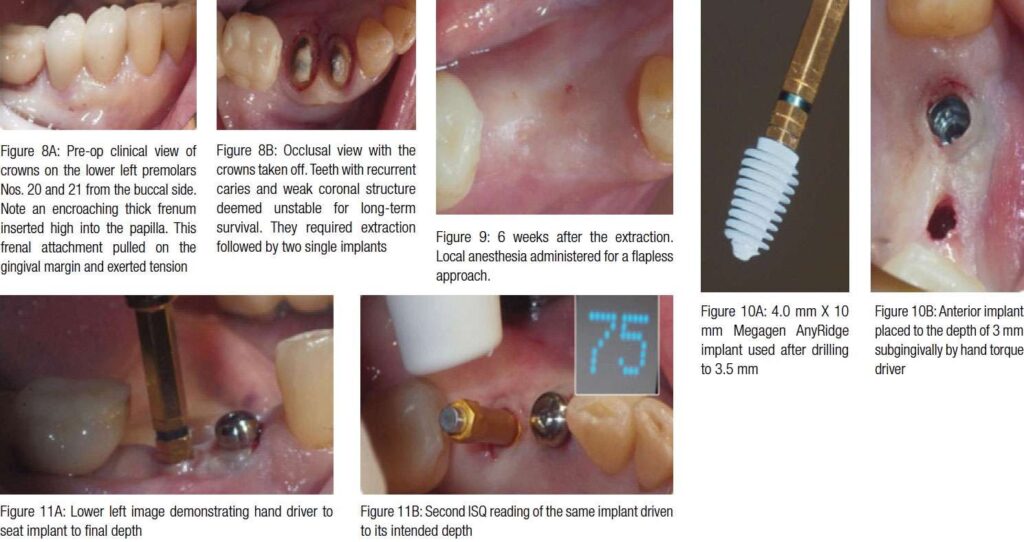

A 75-year-old female patient presented for recurrent caries in the lower left premolars Nos. 20 and 21, underneath crowns (Figures 8A-8B). In addition, the teeth had weak coronal structure. Since they deemed unstable for long-term survival, it was decided to extract them and replace them with two single implants. Six weeks after extraction, the patient returned for a flapless implant placement (Figures 9-11B).

Six weeks after implant placement (the healing phase), the patient came in for the implant crowns loading. Figures 12A and 12B demonstrate healthy appearance of periimplant mucosa. However, horizontal rotation of the labial and buccal tissue revealed tension created by the movable mucosa very close to the implants. This was due to the narrow zone of attached gingival mucosa (this narrow zone is especially noticeable in Figures 10B, 11A, and 12A. The pale pink tissue is the attached gingiva, whereas the bright pink is the movable alveolar mucosa).

It became apparent that the encroaching movable mucosa and the close buccal frenum insertion (clearly seen in Figure 8A), both exerted tension on the peri-implant tissue, especially noticeable when lip or cheek were manipulated. This created potential for tissue recession and could eventually facilitate the implants’ failure. It was decided to perform a CO2 laser frenectomy/vestibuloplasty to alleviate the tension and possibly increase the width of attached gingiva.